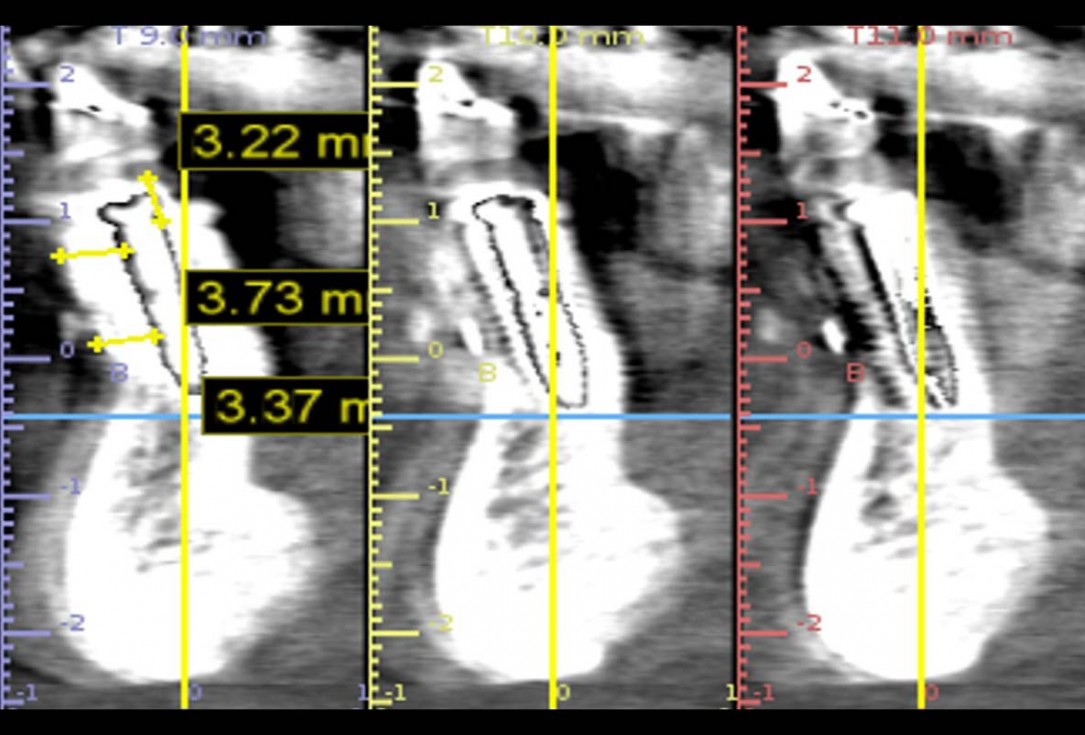

X-ray control before tooth extraction